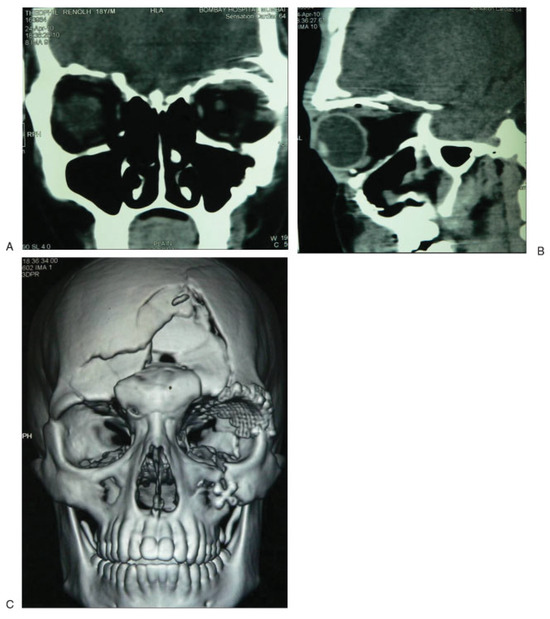

Titanium Mesh Reconstruction of Orbital Roof Fracture with Traumatic Encephalocele: A Case Report and Review of Literature

Case Report